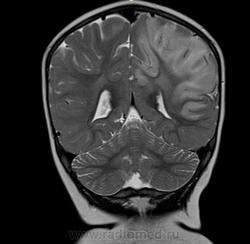

Ребенок 1 год 8 месяцев. В анамнезе с 06.12  многократные рвоты, повышение Т, слабость, сонливость, беспокойство, потиливость. БЫл поставлен диагноз ПТИ, после инфузионнйо терапии, дезинтоксикации в удовлетворительном состоянии выписана. Черезе месяц  гнойные высыпания на конечностях, диагноз пиодермия и дисфункция биллиарного тракта.  Полечили. Дальше в тчеении двух месяцев  однократные-многократные  рвоты, нарушение сна. Невропатолог поставил гидроцефальный синдрмо с тадии субкомпенсации. Ангиоретинопатия. На левой щеке на спине и на коже бедра гематомы в стадии отцветания. Сейчас состояние прогрессивно ухудшается.

Входящий диганоз пишут вирусный менингоэнцефалит. Рекомендуют диффреенцировать со свежими ишемическими изменениями и неопластическим процессом.

А что еще нужно? Диффузия есть, какой-то не очень понятный flair, зона изменений на них идентична Т2ВИ. По РКТ перед этим заподозрили арахноидальную кисту, диф с менингиомой задней трети серпа.

Учитывая возникающие мелкие гематомы на теле и ангиоретинопатию можно предпологать  некую патологию сосудистого русла.

В тоже время, ишемия (инсульт?) по времени (с июня 12г),а так же клиническим проявлениям не очень подходит.   Без отека, борозды сохранены, сдавление вон левого желудка...

Артериальный инфаркт в бассейн не умещается, тут и сма и пма. Синусы на взгляд проходимы. Так что мне кажется больше за энцефалит. Оболочки правда не утолщены (если менингоэнцефалит).

Анамнез не дочитал сначала. За опухоль на мой взгляд данных нет вообще. Изменения идут по коре на большом протяжении с небольшой относительно зоной отёка белого вещества. Так что менингоэнцефалит наиболее вероятен. Анамнез ликвора на мой взгляд обязателен, хотя я и не невролог.

Я бы в дифряд еще гипоперфузию добавил (визуально похоже на PRES, но локализация иная)... Что там с магистральными сосудами? Ангио делали?

MELAS?

А ведь похоже. И клиника, главное,  укладывается. Спасибо, доктор, за интересное мнение!

Масс-эффект есть - присмотритесь к бороздам на Т1. Есть поражение и коры, и белого вещества - такое бывает при нарушении кровотока по мелким сосудам. Снижение диффузии (я так понимаю, ADC снижен?) как раз говорит о цитотоксическом отеке и характерно для инфаркта. Единственное, что смущает - это вовлечение бассейна ПМА. Но, во первых, эти бассейны у людей вариабельны, и вполне может оказаться, что медиальные отделы полушария кровоснабжаются у этого пациента из СМА. А во-вторых, если есть патология сосудов, то почему бы и не поражение 2 бассейнов сразу? Так что, я не вижу тут ничего, что бы не укладывалось в инсульт. А посему пользуемся бритвой Оккама.

Энцефалит как правило двусторонний. Все эти болезни обмена - тоже множественные участки.